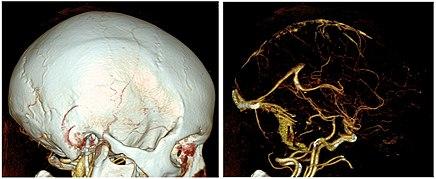

CTA of a vascular malformation with intraventricular hemorrhage.

CTA can be used assess acute stroke patients by identifying clots in the arteries of the brain.[1] It can also be used to identify small aneurysms or arteriovenous malformation inside the brain that can be life-threatening. While CTA can produce high quality images of the carotid arteries for grading the level of stenosis (narrowing of the vessel), calcium deposits (calcified plaques) in the area where the vessels split can lead to interference with accurate stenosis grading. Because of this, magnetic resonance angiography is used more often for this purpose.[2]

In volume renderings, automatic bone removal (used in the right image) is helpful for visualizing the intracranial vessels.

CT angiography is a contrast CT where images are taken with a certain delay after injection of radiocontrast material. The contrast material is radiodense causing it to light up brightly within the blood vessels of interest. In order for the CT scanner to be able to scan the correct area where the contrast is, the scanner uses either automatic detectors which start scanning when enough contrast is present, or small test boluses. With the small test bolus, a small amount of contrast is injected in order to detect the speed that the contrast will move through the blood vessels. After determining this speed, the full bolus is injected and the scan is begun at the timing determined by the test bolus. After the scan is completed the images are post-processed to better visualize the vessels and can even be created in the 3D images.[6]